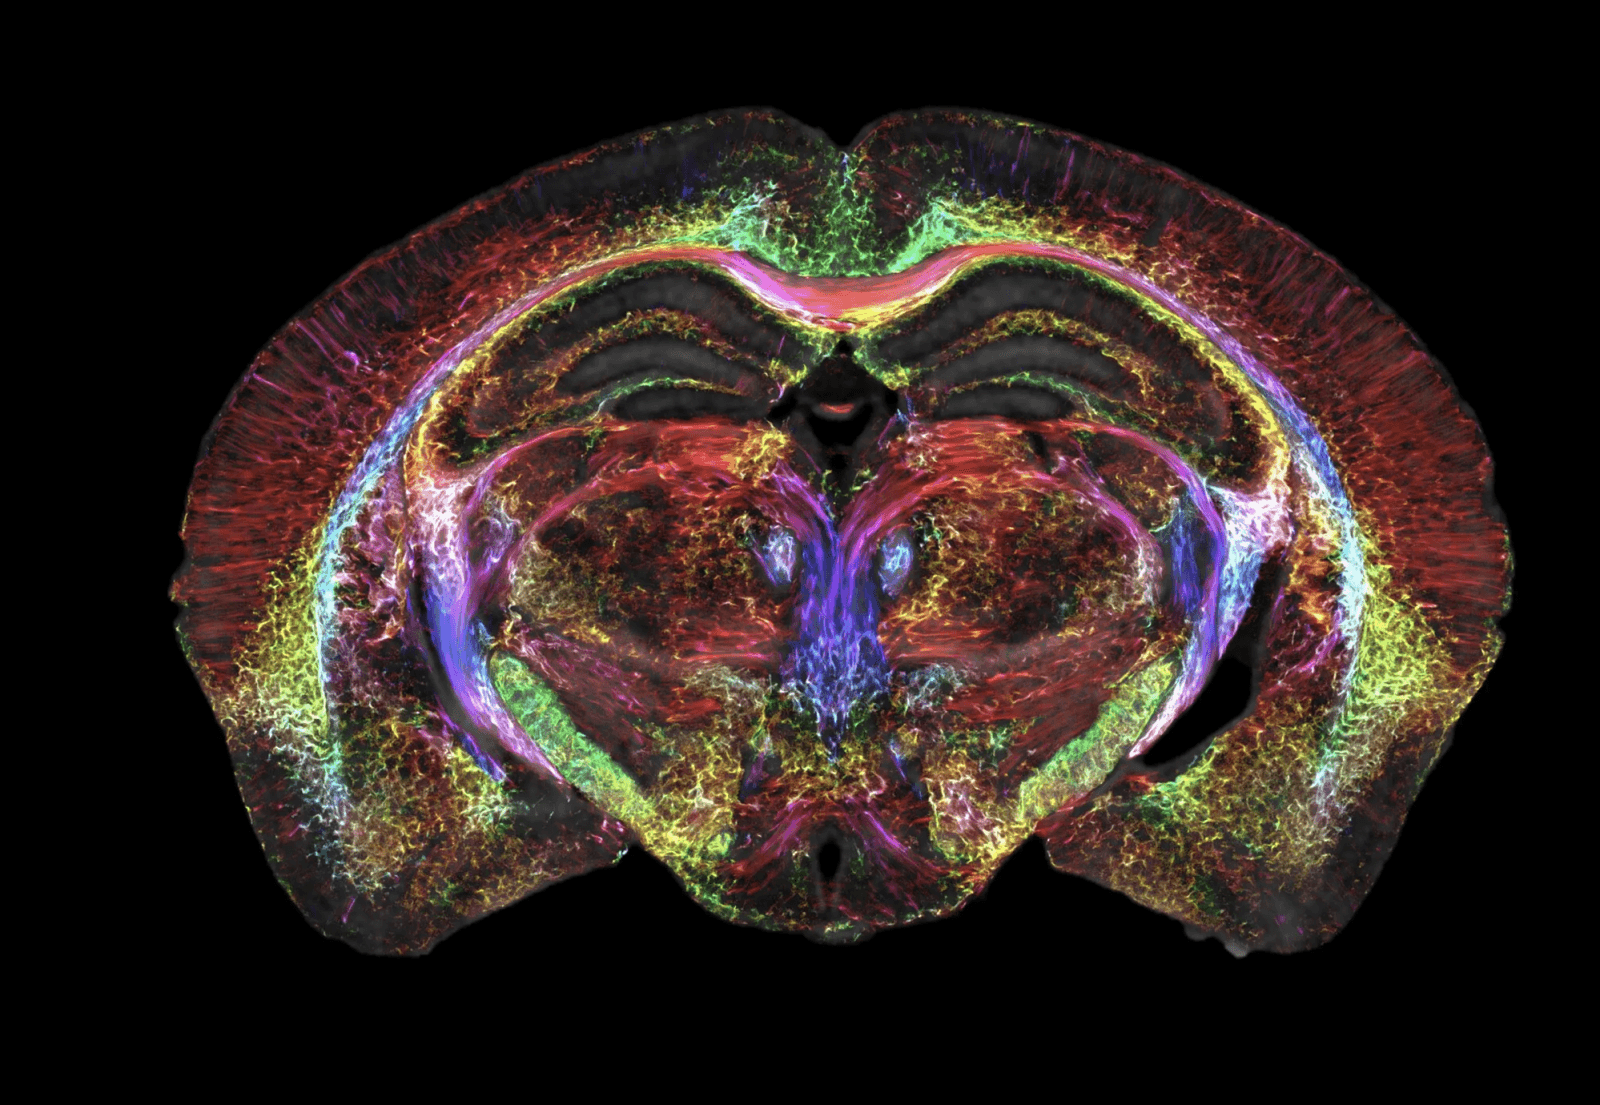

Naukowcy z Duke’s Center for In Vivo Microscopy we współpracy z badaczami z University of Tennessee Health Science Center, University of Pennsylvania, University of Pittsburgh i Indiana University, poprawili rozdzielczość MRI i uzyskali najostrzejsze skany mózgu myszy w historii. Zbiega się to w czasie z 50. rocznicą pierwszego wykonanego rezonansu magnetycznego. Praca, która ukazała się w Proceedings of the National Academy of Sciences (PNAS), jest zwieńczeniem prawie 40 lat badań prowadzonych w Duke Center for In Vivo Microscopy.

Uczeni stworzyli skany 3D mózgu myszy z zachowaniem wręcz hiperrealistycznej szczegółowości. Pojedynczy woksel (odpowiednik piksela w grafice 3D) mierzy zaledwie 5 mikronów, a to aż 64 miliony razy mniej niż woksel w klinicznym MRI!

Mimo iż badania przeprowadzono na gryzoniach, to udoskonalony rezonans magnetyczny pozwoli na wizualizację połączeń w całym mózgu z rekordową rozdzielczością. To z kolei może całkowicie zrewolucjonizować neurologię i pozwoli zrozumieć, jak mózg zmienia się z wiekiem, dietą, a nawet różnymi chorobami.

Ale jak właściwie udało się ulepszyć badanie MRI? Większość klinicznych rezonansów magnetycznych wykorzystuje magnesy o mocy od 1,5 do 3 Tesli, a zespół prof. Johnsona użył urządzenia o mocy aż 9,4 Tesli. Do tego dochodzi specjalny zestaw cewek gradientowych – 100 razy silniejszych od tych z maszyn stosowanych w szpitalach, a także superwydajny komputer, który mocą odpowiada prawie 800 laptopom pracującym nad obrazem tylko jednego mózgu. Dzięki temu naukowcy mogą odkrywać tajemnice mózgu w sposób, który nigdy wcześniej nie był możliwy.